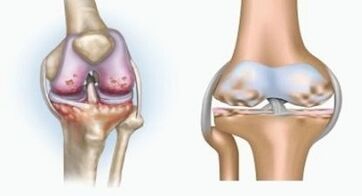

И двете патологии засягат ставите, но се различават по естеството на промените.

С артрит

Артритът е възпаление на съединителната тъкан - синовиална мембрана, която съдържа много съдове и осигурява лимфния поток. Възпалителният процес води до нарушаване на храненето на ставните тъкани, в резултат на което производството на ставно смазване - синовиалната течност е ограничено.

С артроза

Артрозата е дегенеративно-дистрофичен процес, свързан с унищожаването на хрущялната тъкан на ставата. Хрущялът постепенно се унищожава, сухо, разстоянието между костите на ставата намалява, което е причината за болката. При тежки форми унищожаването засяга костите. Те стават по -порести, губят плътността си, стават крехки.

Например, каква е разликата между артрит и артроза на колянната става? С артрит се появява синовиалната обвивка на ставните тъкани. Това води до повишаване на температурата в ставата.

Ставата набъбва, се развива постоянен синдром на болката, засилвайки се по време на движение. С артрозата болката възниква само след физическа активност, можете да чуете характерна криза или кликвания в ставата, постепенно ставата се деформира и губи мобилност.